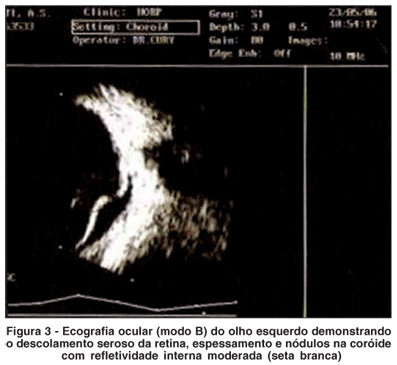

Paciente de 65 anos do sexo feminino com história de baixa da acuidade visual progressiva no olho esquerdo há 8 meses. A paciente negava antece dentes familiares e apresentava, como antecedentes patológicos, cardiopatia chagásica, hipertensão arterial sistêmica, histórico de tabagismo durante 30 anos. Ao exame oftalmológico, a acuidade visual com a melhor correção era 20/20 em olho direito e contar dedos a 50 centímetros em olho esquerdo, ausência de defeito pupilar aferente e tonometria de aplanação de 15 mmHg em ambos os olhos. A fundoscopia do olho direito não apresentava alterações e o olho esquerdo apresentava quadro de: dispersão pigmentar pela retina, nodulações difusas ao nível da coróide, descolamento seroso da retina (DRS) e edema do disco óptico (Figura 1). O corpo vítreo apresentava-se acelular em ambos os olhos. O exame angiofluoresceinográfico demonstrou aspecto tigróide, tipo "leopard spots", com áreas de hipofluorescência por bloqueio pigmentar permeadas por áreas de hiperfluorescência transmitida. O disco óptico, na fase inicial, apresentava extravasamento do contraste o qual acentuou-se nas fases mais tardias (Figura 2). A ecografia ocular no modo A e B demonstrou a presença de imagens hiperecogênicas ao nível da coróide com média refletividade interna (Figura 3). A tomografia de coerência óptica (OCT) revelou imagens hiperrefletivas ao nível da coróide, nos locais onde haviam nodulações à fundoscopia, ruptura do epitélio pigmentado da retina (EPR) e áreas de hiporrefletividade sub-retinianas compatíveis com o DRS (Figura 4). Solicitamos avaliação sistêmica para a detecção de neoplasia primária ou de doença granulomatosa. O exame físico realizado apresentou-se normal. Os exames laboratoriais solicitados, tais como: hemograma, coagulograma, Enzima conversora da angiotensina (ECA) e sorologia para sífilis, não revelaram nenhuma alteração. Foram solicitados exames radiológicos como: radiografia de tórax, que revelou a presença de imagem radiopaca ao nível do ápice pulmonar esquerdo e aumento da área cardíaca (Figura 5A), mamografia sem alterações e ressonância nuclear magnética torácica demonstrando a presença de lesão tumoral no parênquima pulmonar, contínua com a pleura, na região do ápice pulmonar esquerdo (Figura 5B e C).

A efusão uveal pode ocorrer como resultado de processo inflamatório, anormalidades esclerais ou aumento da pressão na circulação coroidal(1). Alguns autores propuseram que o descolamento cilio-coroidal seria causado por hipotonia, inflamação intra-ocular e/ou tumores intra-ocu lares(9). Estes devem ser sempre lembrados, como diagnóstico diferencial, nos casos de síndrome de efusão uveal secundária. Neste caso em questão, relatamos um paciente com quadro similar à efusão uveal secundário a carcinoma metastático da coróide, porém sem apresentar alterações ecográficas compatíveis com a síndrome. Um relato de caso(10) demonstrou a manifestação de um carcinoma metastático da coróide como efusão uveal, acompanhada dos sinais clássicos como descolamento da coróide, ao exame ecográfico, e "leopard spots". A metástase uveal é o tumor intra-ocular mais comum(2-4), sendo a coróide o local mais acometido. O diagnóstico do carcinoma metastático da coróide é desafiador, quando se desconhece a presença de um tumor primário(8). Esses autores demonstraram, em um estudo, que o foco primário já era conhecido antes do diagnóstico de carcinoma metastático da coróide em 66% dos casos. Dos 34% restantes, o sítio primário foi identificado em 49%, sendo o pulmão responsável por 70% destes casos(8). O exame fundoscópico, do olho esquerdo, demonstrava a presença múltiplos nódulos na coróide, descolamento seroso da retina e alterações no EPR. Vários tipos de lesões podem simular o carcinoma metastático da coróide, tais como: melanoma de coróide, osteoma de coróide, hemangioma de coróide, neovascularização da coróide com cicatriz disciforme e sarcoidose. O envolvimento do segmento posterior por sarcoidose ocorre em 25% dos casos e geralmente se manifesta como coriorretinite multifocal e periflebite retiniana(8,11). Outra forma, menos comum, é o granuloma solitário de coróide(12). Situações inflamatórias como: doença de Harada, síndrome da efusão uveal idiopática e esclerite posterior também devem ser incluídas no "pool" de diagnósticos diferenciais. Nestes casos inflamatórios geralmente há presença vitreíte e espessamento da coróide, observado ao exame ecográfico. Neste caso, o padrão "leopard spots", típico da síndrome da efusão uveal, foi encontrado no exame angiofluoresceinográfico. O exame ecográfico revelou DRS inferior, espessamento de coróide e presença de nódulos de média refletividade interna. O carcinoma metastático da coróide, secundário ao câncer de mama, geralmente se apresenta como uma ou mais lesões sésseis, com pouca elevação e infiltrados amarelados. Os casos de carcinoma metastático da coróide por câncer pulmonar podem ter estas características porém, mais freqüentemente, as lesões são mais elevadas, cupuliformes e semelhantes ao melanoma primário da coróide(13). No caso em questão, observamos uma apresentação menos comum, do carcinoma metastático da coróide por tumor pulmonar, com múltiplos nódulos coroidianos. Em um estudo realizado em 520 olhos a distribuição em relação ao sítio primário do carcinoma metastático da coróide, no sexo feminino foi: mama em 67%, pulmão 12%, desconhecido em 12%, gastrointestinal em 2% e pele em 1% dos casos. Estudos clínicos e histopatológicos de pacientes com carcinoma metastático da coróide demonstram alterações secundárias que incluem: descolamento seroso da retina que geralmente extrapola os limites do tumor, atrofia do EPR e da retina, degeneração cistóide da retina levando a quadros de retinosquise e invasão da retina neurosensorial pelo tumor(8,14-15). O OCT pode mostrar claramente as alterações estruturais na retina, que circunda o tumor de coróide, embora não forneça nenhuma informação sobre sua histopatologia(16). Autores demonstraram, através de estudo tomográfico em 7 olhos com carcinoma metastático da coróide, alterações características da retina e do complexo EPR-córiocapilar(15). Os achados mais encontrados foram áreas de hiporrefletividade correspondentes ao DR seroso e lesões hiperrefletivas sobre o complexo EPR-córiocapilar em 87,5% dos casos. Neste caso o OCT demonstrou a presença de rotura do EPR, além de algumas lesões descritas neste estudo. Através deste relato concluímos que, o papel do oftalmologista é primordial, em algumas situações, no diagnóstico de tumores sistêmicos que se apresentam como metástase coroidiana. Na presença de quadro clínico-angiográfico, semelhante ao da efusão uveal, deve-se afastar a hipótese de carcinoma metastático da coróide.